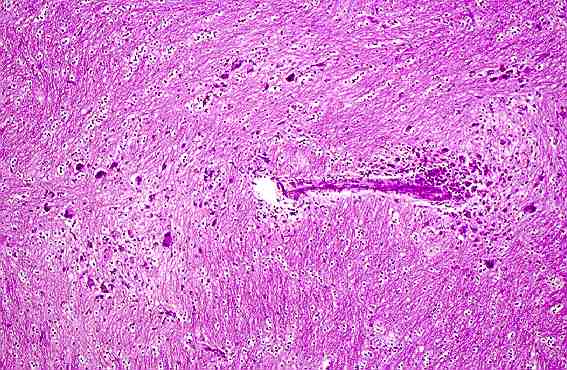

mgut04.jpg (47894 bytes)

4.- Apariencia microgranulomatosa de una lesión en substancia blanca.